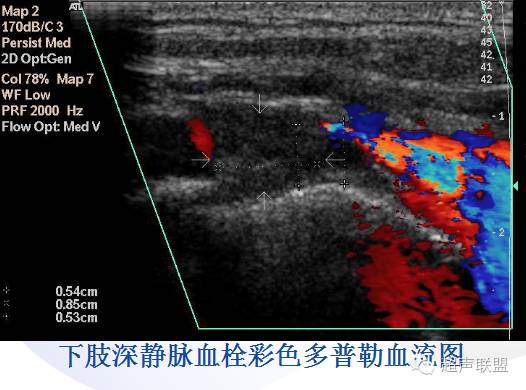

下肢静脉血栓远较上肢多见。

下肢静脉血栓:髂外静脉血栓,股静脉血栓,腘静脉血栓,小腿深静脉血栓,小腿肌肉静脉丛血栓。

* 四肢静脉血栓的超声诊断标准如下:

主要标准

1、 管腔不能被压瘪(压迫试验)

2、 管腔内实质性回声

3、 管腔内血流信号充盈缺损